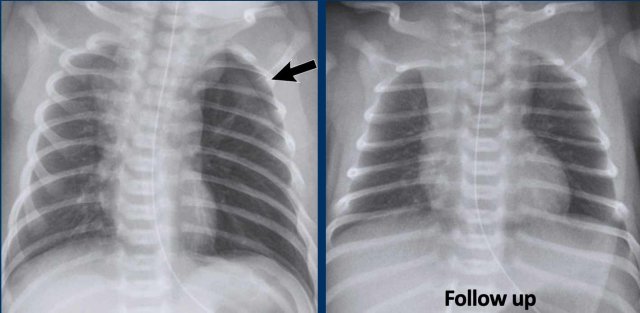

These images are of a neonate gestational age 32 weeks, who was treated for RDS.

Several complications developed, including a pneumothorax on the left side, which was drained.

After drainage there was a deterioration.

Image 1

The radiograph shows bilateral radiating bubbly lucencies due to bilateral PIE.

This is more pronounced on the left side.

Image 2

In follow up the child also developed a pneumothorax on the right side.